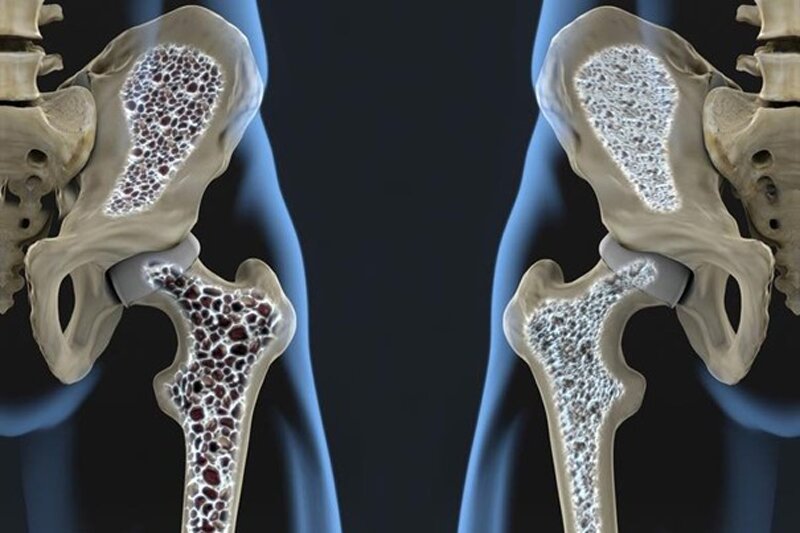

دکتر فاطمه حاجی ولیزاده با اشاره به اینکه پوکی استخوان یک بیماری خاموش است، گفت: این بیماری مختص اواخر سنین میانسالی و سالمندی است که با مینرالیزه شدن استخوان اتفاق میافتد و سبب میشود استخوانها متخلخل و شکننده شوند. در واقع ساختار استخوان بهم میخورد و ماده معدنی آنها کم شده و استخوان استحکام خود را از دست میدهد؛ در نتیجه استخوان با کوچکترین ضربهای که انتظار نمیرود، دچار شکستگی میشود.

وی افزود: پس خود پوکی استخوان یک بیماری است که در ظاهر علامتی ندارد و زمان بروز شکستگی، تازه علائم آن مشاهده میشود. با توجه به اینکه بیشتر استخوانهایی که پوک میشوند شامل استخوان ستون فقرات، استخوان لگن و سر استخوان ران و ساعد است، شکستگیها هم بیشتر در این نقاط رخ میدهد. بروز شکستگی سبب ناراحتی و محدودیت حرکتی میشود؛ بنابراین در سنین بزرگسالی با سالمندانی مواجه میشویم که قدشان کوتاهتر شده است و این موضوع هم به واسطه این است که ستون فقراتشان دچار شکستگی شده و یا روی هم خوابیده است و این یکی از علائم پوکی استخوان است.

وی افزود: به طور کلی با دو واژه استئوپروز (پوکی استخوان کامل) و استئوپنی (از دست رفتن چگالی استخوان البته نه در حد پوکی استخوان کامل) از بروز پوکی استخوان منجر به شکستگی یاد میشود. ۶۰ درصد افراد بالاتر از ۵۰ سال ایرانی دچار استئوپروز و استئوپنی هستند و از هر ۳ خانم بالاتر از ۵۰ سال و از هر ۵ مرد بالاتر از ۷۰ سال یک نفر دچار شکستگی ناشی از پوکی استخوان میشود.